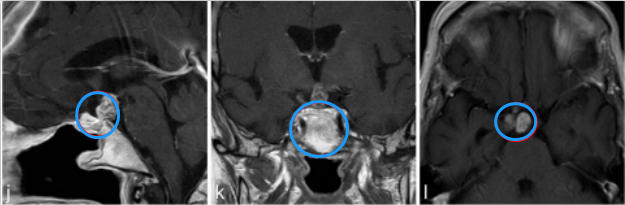

j、k、l图显示,肿瘤得到全切,术后2年没有复发,目前孩子在接受激素替代疗法

j-l图表示,在3个月后复查MR检查,显示术后垂体柄处有肿瘤少量残留。

m-o图显示,磁共振成像分期立体定向放射治疗后22个月,显示肿瘤明显缩小。病人经氢化可的松和甲状腺激素的替代治疗恢复良好。